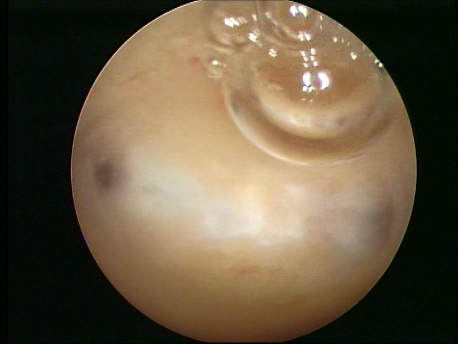

- Infertility and recurrent loss (Subfertility): Infertility means the inability to conceive and recurrent pregnancy loss means loss of 3 or more (in practice, usually 2 or more) consecutive early pregnancy (less than 5 months). Uterine pathology such as abnormal shape (septum or the T shaped uterus), submucous fibroids or polyps, and intrauterine adhesions can cause subfertility. Tubal block due to spasm or mucus plugs can contribute to infertility and can be opened by hysteroscopic cannulation.